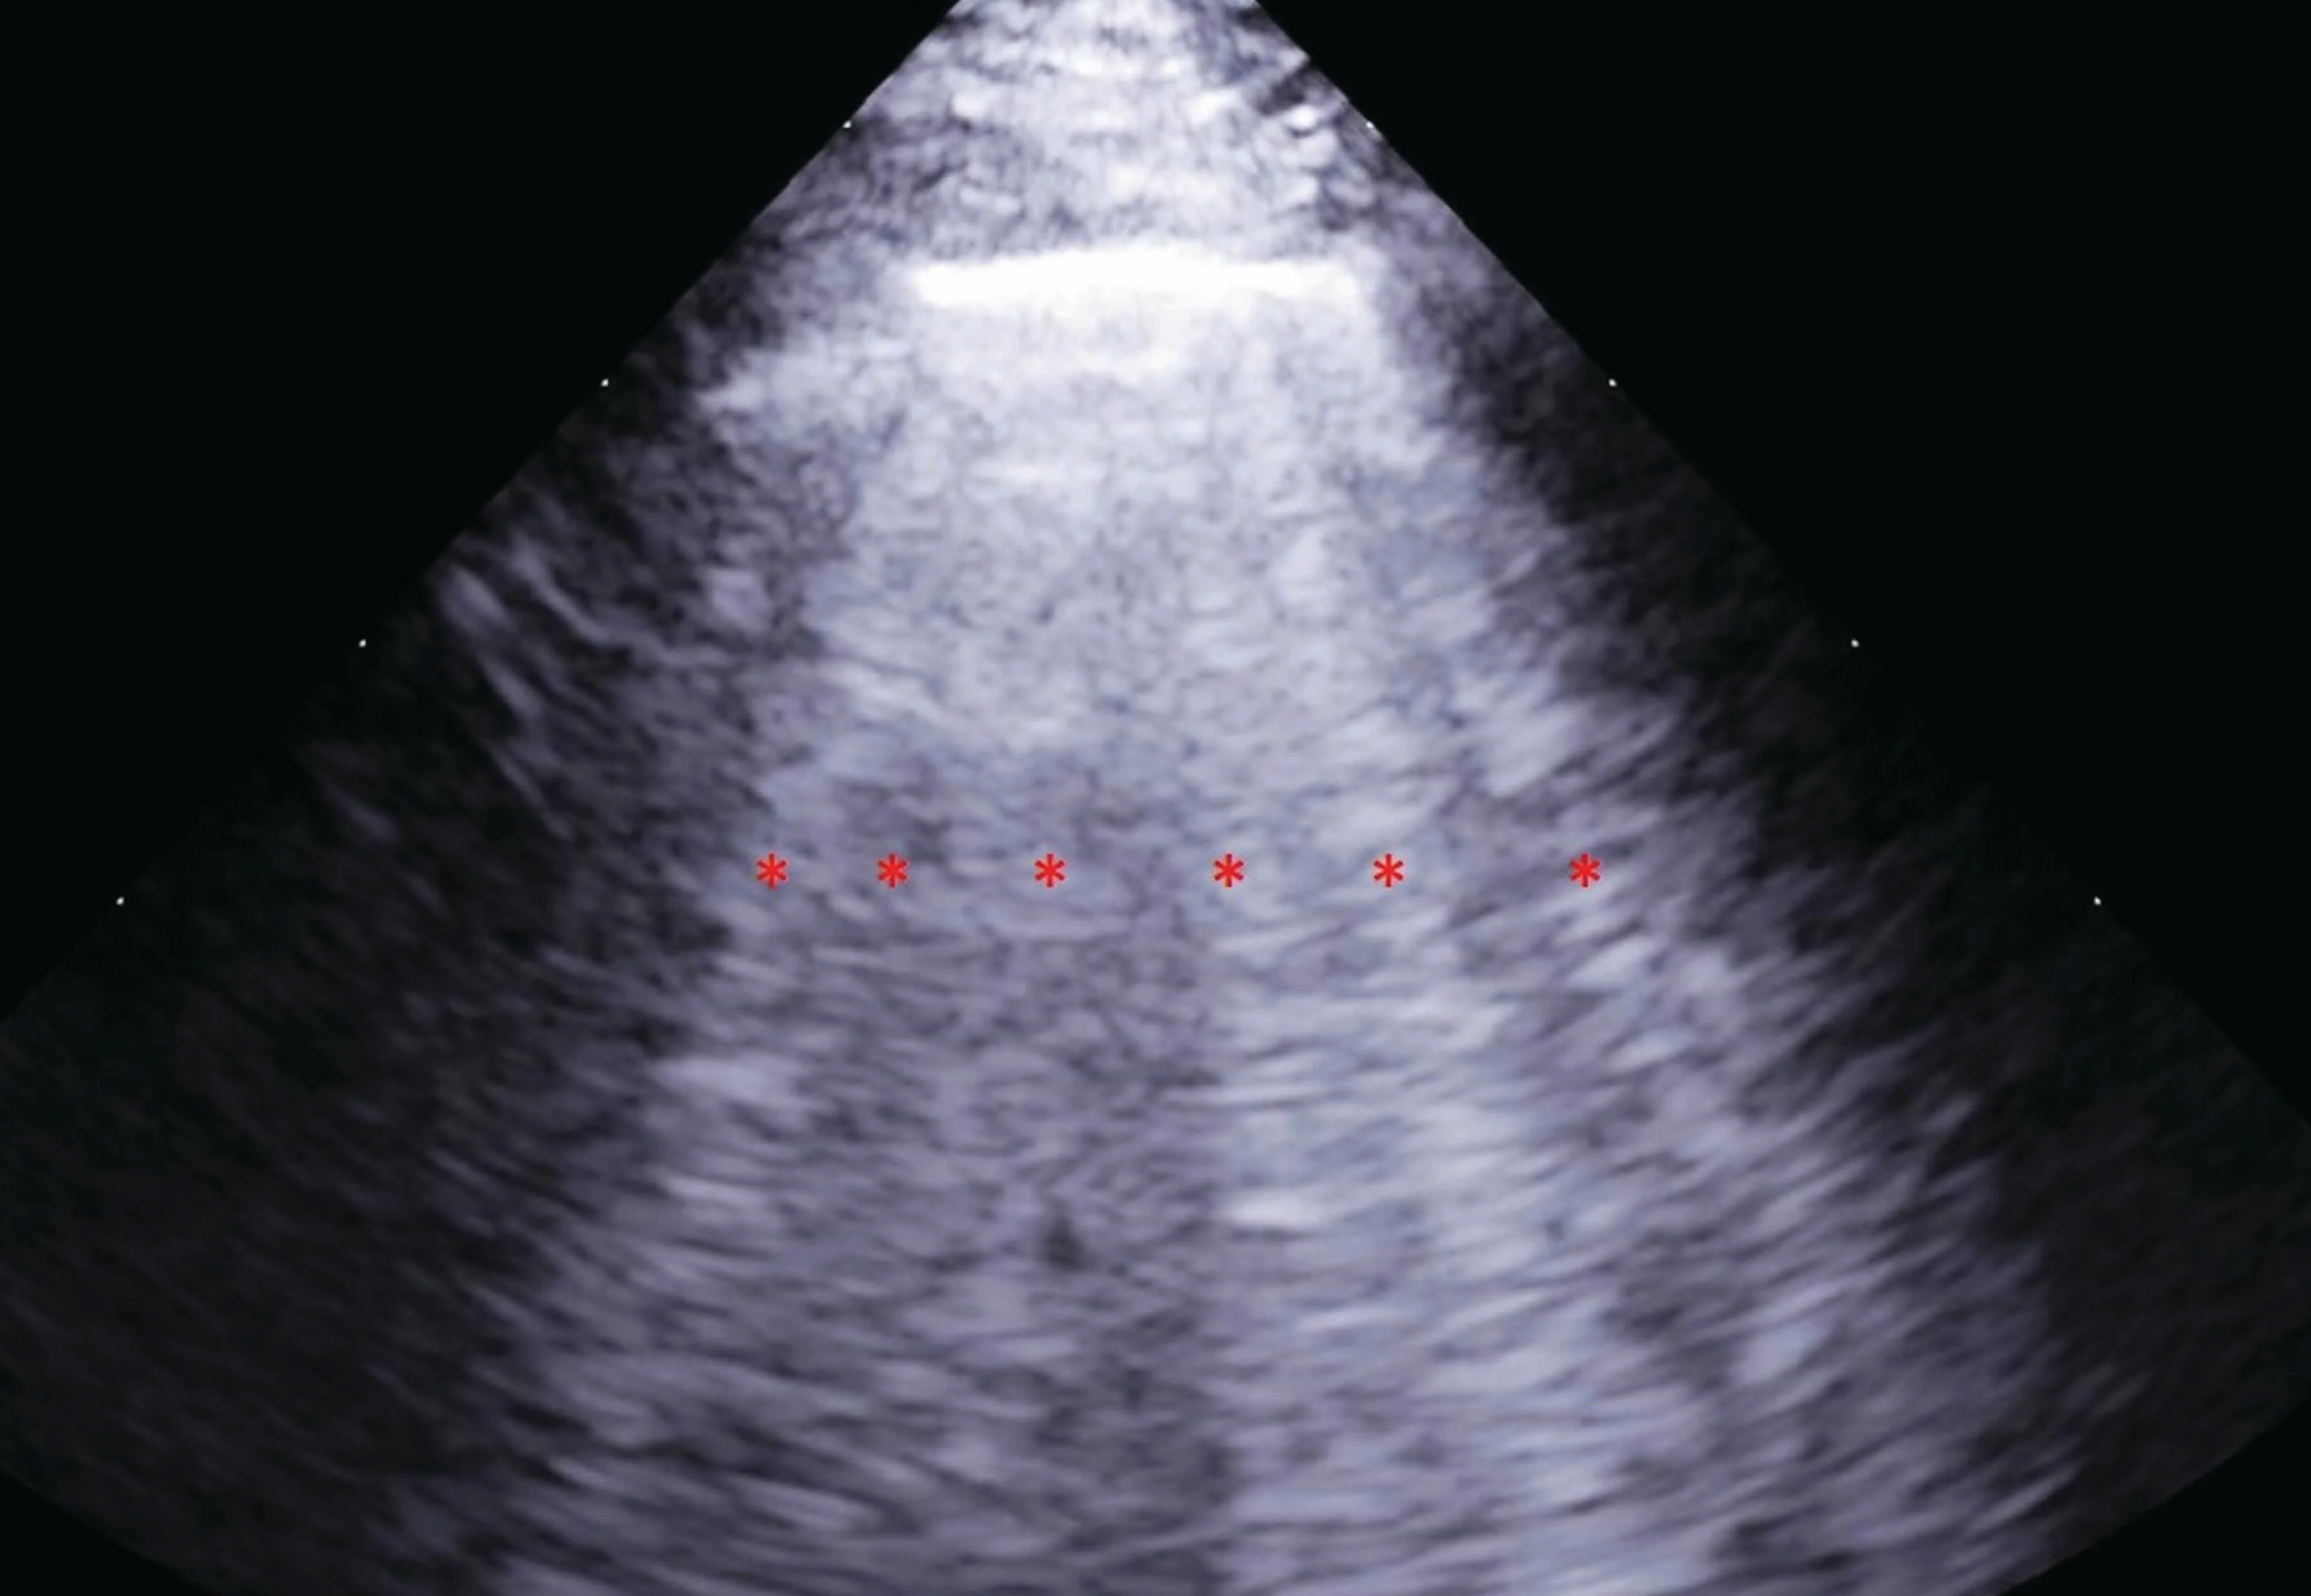

Respiratory Distress: Increased breathing rate and effort are common indicators, suggesting fluid buildup in the lungs or chest cavity, a hallmark of congestive heart failure (CHF).

Fluid Retention: Excessive fluid accumulation in the body is a direct consequence of the heart's failing pump function.